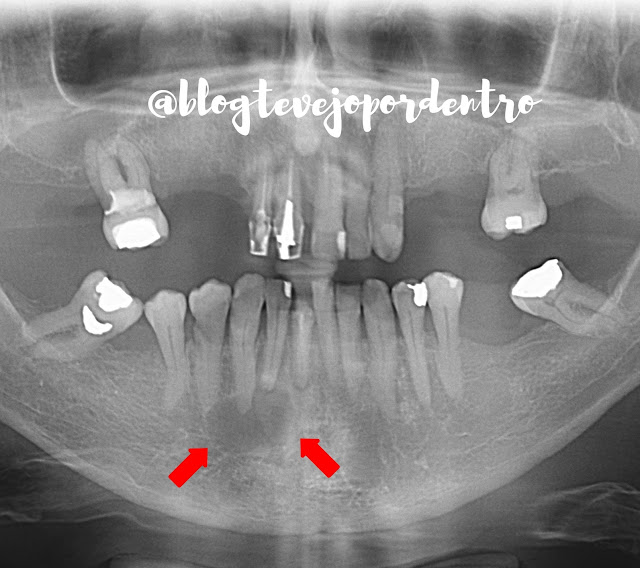

Lesão com aspecto cístico